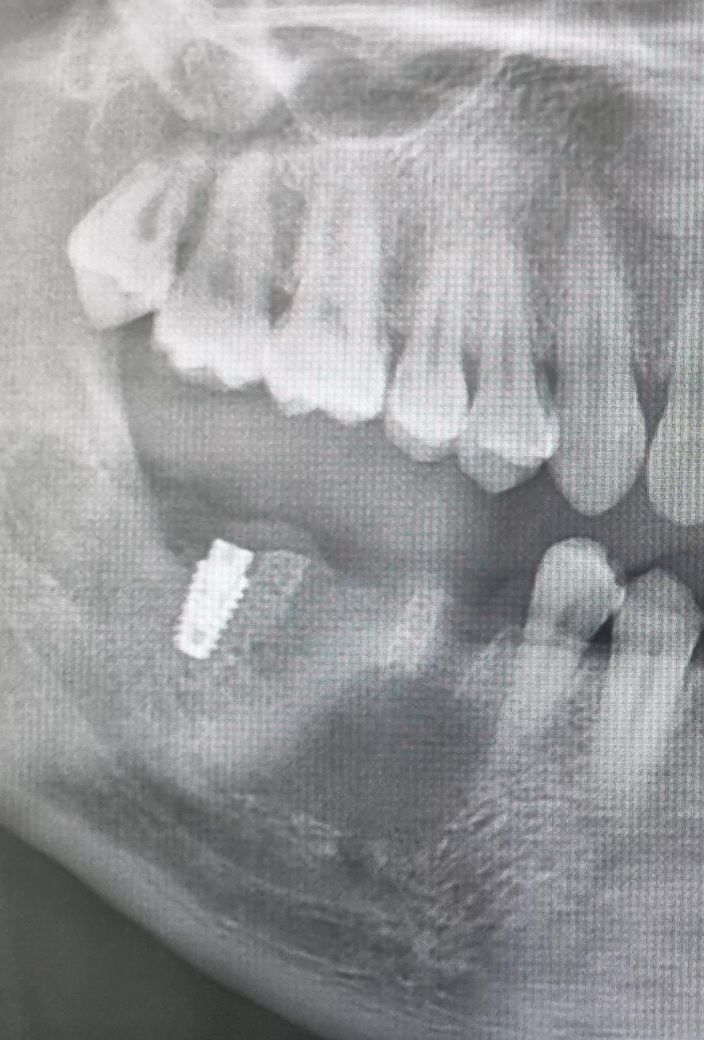

올초에 맨 끝 어금니 뿌리쪽 크랙이 있어 치아를 뽑고 임플란트를 진행하는 중에, 옆 어금니에 통증이 있어 엑스레이를 찍어보니 염증이 있어 급히 치아 2개를 추가 발치했습니다.(첫번째 사진과 같이 염증이 커서

통증 부위 옆 치아까지 발치)

그렇게 10월 치아 2개발치 후 11월에 입원 수술해서 염증을 제거하고 조직검사하니 육아낭종이라고 하더라구요.

• 1번 째 사진